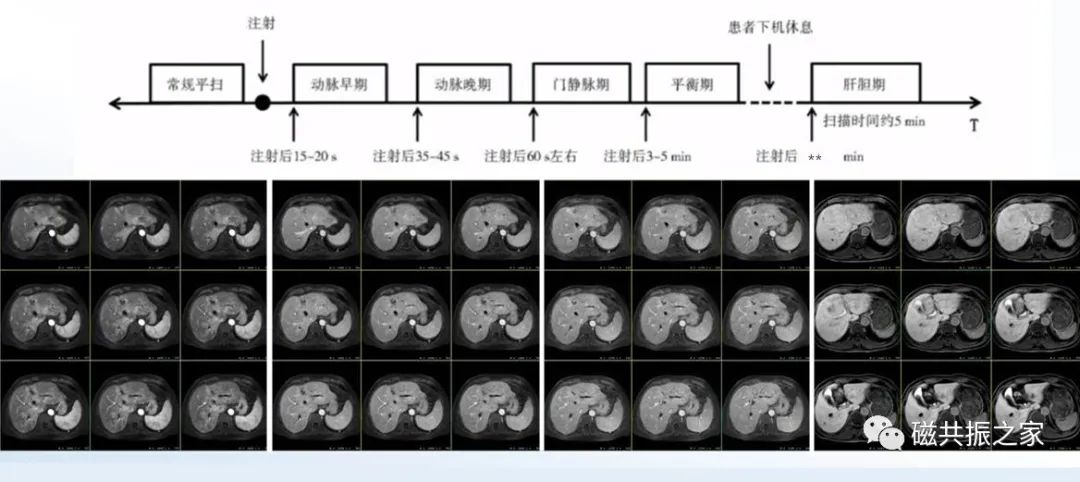

增强扫描

横轴面:横轴面多期动态增强扫描序列

在矢状位和冠状位上定位。扫描范围上至肝顶,下至十二指肠,合理调整扫描范围,需包括整个病变范围。

5.如采用的是肝胆特异性对比剂,肝胆期延迟扫描的时间应根据使用的对比剂类型和个体差异合理调整。

正常肝组织的信号高于血管信号,且胆系明显显影,即是较为合理的肝胆期图像。

肝硬化、肝功异常、胆道病变等,建议120min后扫描,缺乏血供小结节可延迟至3h。

同时,研究表明对于肝硬化患者,其3h后的肝胆期显示效能高于60min后的图像。

对于肝硬化、代谢异常的患者应适当延迟,建议40min后扫描。